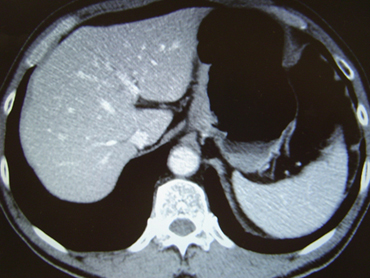

(d) CT検査

- がんの深さを調べたり,周辺組織との関係を調べたり,リンパ節転移の有無,遠隔転移の有無を調べます。発泡剤を服用して造影剤を注射して撮影します。